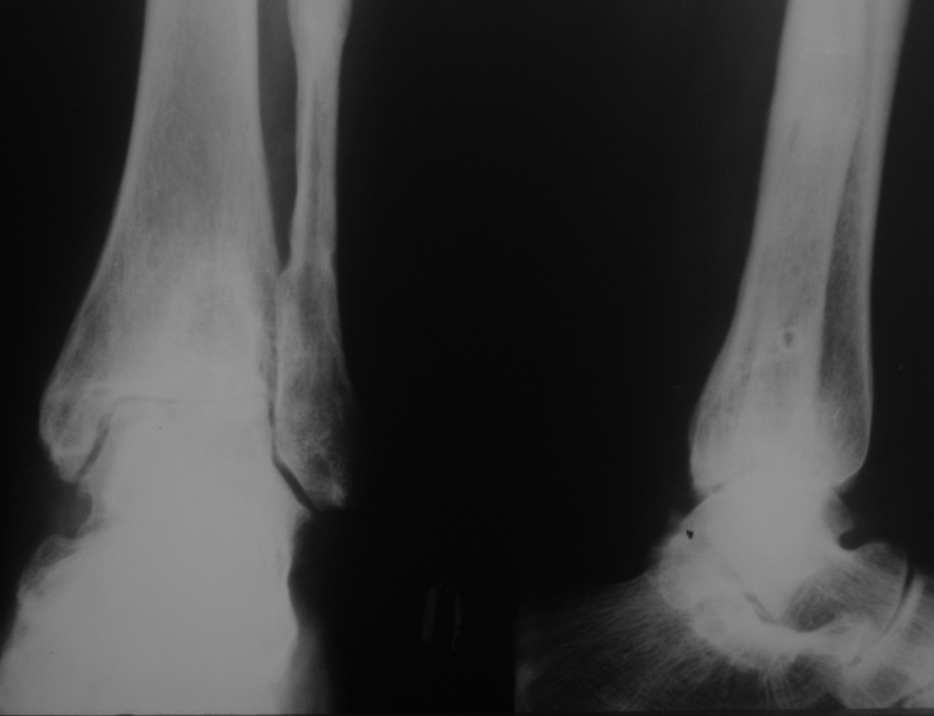

Уважаемые коллеги, разъясните ситуацию.Пациентка, 45лет. 9 месяцев назад произведен синтез

двухлодыжечного перелома правой голени.

Конструкции на данный момент удалены. Объем движений на фото. Сейчас беспокоят скованость в области сустава, боли к концу рабочего дня - классическая клиника артроза.Пропила 4 курса найз. Откуда артроз такой выраженности (на рентгенограмме)? Поможет ли консервативное лечение и какое поможет наверняка?